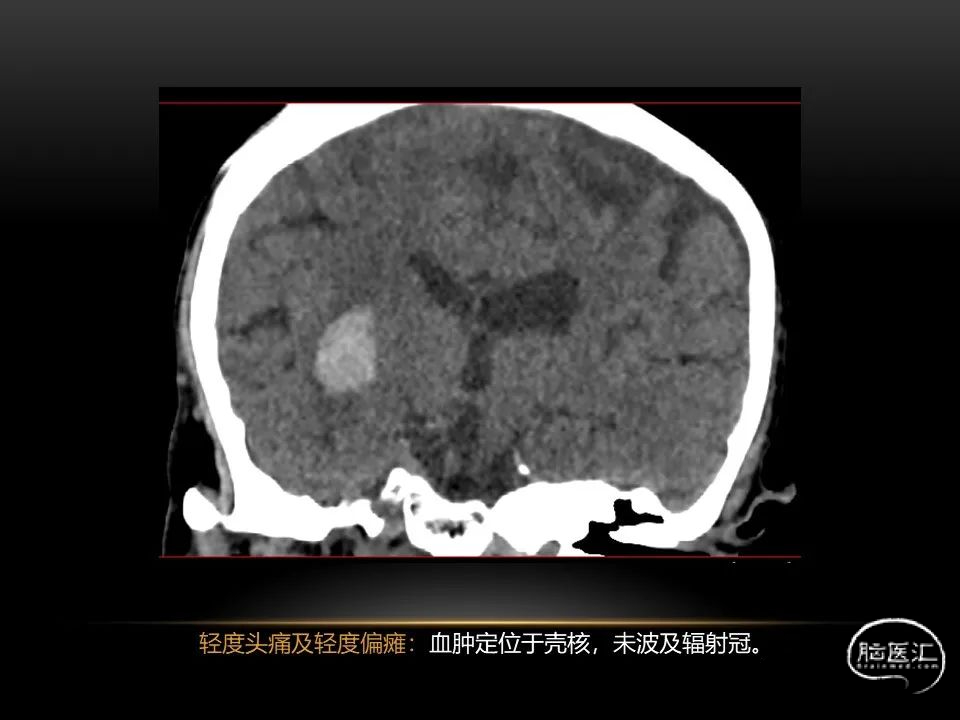

相近的脑出血量,

发生在不同部位有截然不同的症状,

同样也决定了预后也是截然不同的。

自发性脑出血临床上很常见,不同原因有特征性的出血部位。例如:基底节出血和丘脑出血大多是高血压性脑出血;脑叶出血,特别是多次复发的脑叶出血多见于老年人的脑血管淀粉样变。

自发性脑出血不仅仅累及内囊后肢才会出现偏瘫及偏身感觉障碍,病变累及大脑脚或辐射冠同样有可能有类似症状和体征。内囊、辐射冠、大脑脚等结构之间是延续的,只是不同区域不同名称而已。定位诊断需要对解剖结构概念清晰,读片准确辨认,灵活掌握。